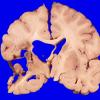

Infarct, Tract Degeneration, illustrative case (2)